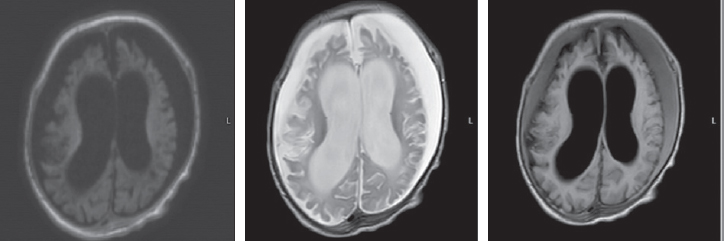

At the age of three months, an MRI of the brain revealed symptoms of delayed myelination, including an increase in the magnetic resonance signal of the posterior parts of the globus pallidus on both sides (Fig. 2).

Fig. 2. Magnetic resonance imaging of a patient at the age of 3 months. Axial sections, T1 VI, T2 VI, Flair. The signs of delayed myelination, were found to be symmetrical at the level of the perirolandic region. The architectonics of the furrows and convolutions have not been changed

Рис. 2. Магнитно-резонансная томограмма пациента в возрасте 3 мес. Аксиальные срезы, Т1ВИ, Т2 ВИ, Flair. Выявлены признаки задержки миелинизации, симметричные на уровне перироландической области. Архитектоника борозд и извилин не изменена